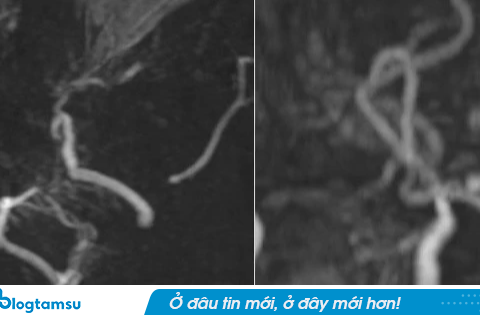

<!– –> Kết quả chụp MRI của 1 bệnh nhân bị đau đầu cho thấy mạch máu não của bệnh nhân mờ như “khói thuốc”. Ngày 27 tháng 9 năm 2025, tạp chí Thanh Niên Việt đã đăng tải tài..